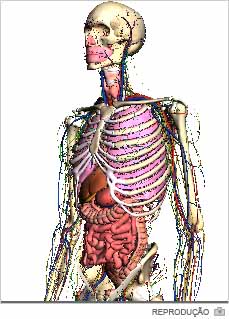

Viajar pelo corpo humano não é mais uma opção de filme de ficção científica, tampouco está restrito a médicos. O conhecimento interno dos músculos, ossos e demais sistemas está disponibilizado pelo Google em três dimensões. O serviço se aparenta com a navegação de alguns mapas. É possível selecionar camadas diferenciadas na visualização.

Trata-se de uma chance, por exemplo, de professores conseguirem tornar a aula de biologia ainda mais interessante devido a interatividade do Google Body (bodybrowser.googlelabs.com). No canto esquerdo, a tela apresenta diferentes opções para a visualização do modelo, seja feminino ou masculino. E, no lado direito, links permitem o compartilhamento e a criação de anotações.